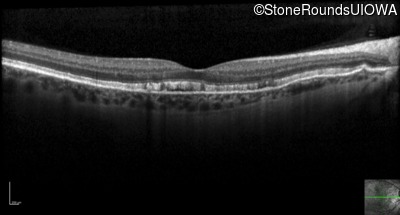

Optical Coherence Tomography - Right - 20/20 -3 sc

Exemplar / OCT Stack